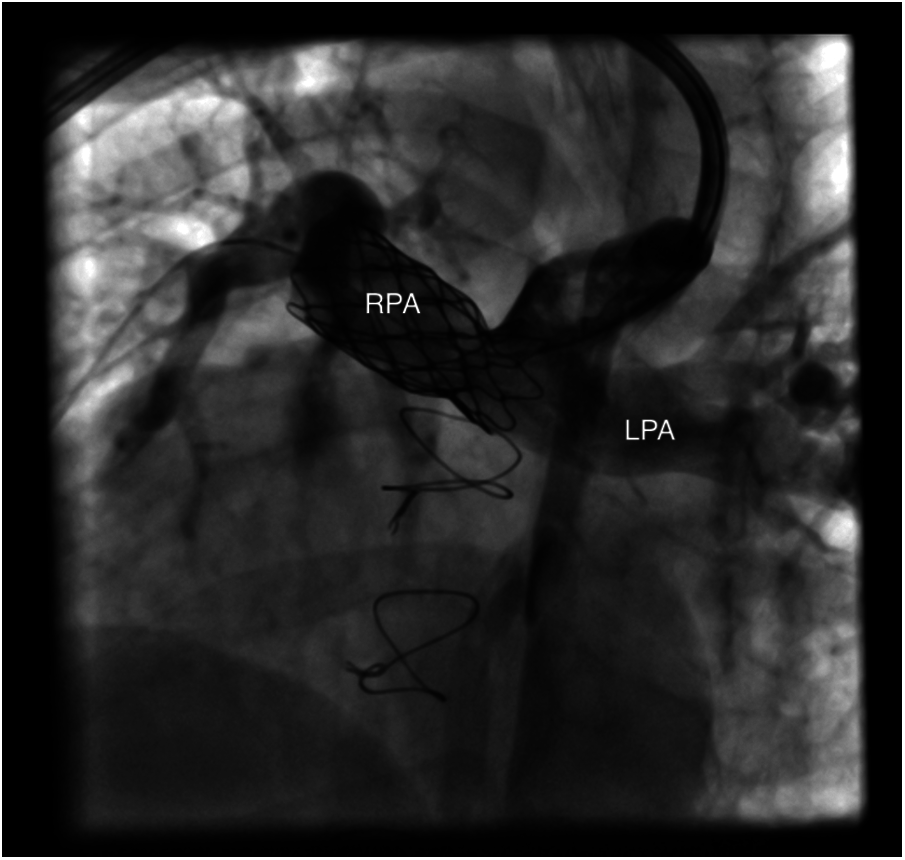

2.6.2 Percutaneous Interventions

Percutaneous interventions were done to few patients and most commonly indicated for peripheral pulmonary stenting or collaterals closure (Fig. 4).

Figure 4: Showing well deployed RPA stent in patient number 10 (RPA: right pulmonary artery, LPA: left pulmonary artery)